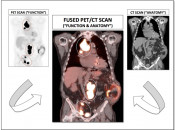

A PET/CT scan is a hybrid imaging study that combines a PET scan’s ability to demonstrate metabolic activity (“a functional exam”) with the CT scan’s ability to define precise anatomic detail (an anatomic exam).

While PET/CT imaging is useful in a number of clinical settings, including cardiac and dementia imaging, its most common use (and the use for which PETCTMD was created) is in the field of Oncology. [Fig. 1]  [Fig. 2]

CT Portion of the Exam:  Its value lies in its excellent anatomic detail, as demonstrated in the case above.  In this patient presenting for post-treatment assessment of lymphoma, the CT clearly demonstrates abnormal soft tissue density above and below the diaphragm.  From the CT scan, we know abnormal soft tissue exists, its size and precisely where it is located. What we do not know from the CT scan is the answer to the ultimate clinical question: Does this remaining soft tissue represent active malignancy or post-therapeutic scarring — Does this patient still have cancer? For the answer, we must turn to the PET portion of the examination.

PET Portion of the Exam: Although of extremely limited anatomic value, the PET study has the impressive ability to determine whether the residual soft tissue on the CT scan represents active malignancy or post-therapeutic scar tissue. In this case, the intense metabolic activity is consistent with active lymphoma both above and below the diaphragm.

Fused Images: The impressive power of PET/CT is dramatically illustrated when we fuse the “anatomic” CT images with the “functional” PET images, revealing an elegant anatomic map of all active disease.